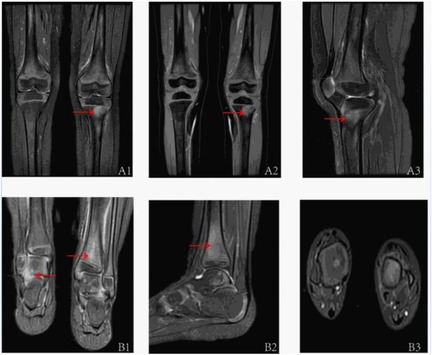

Extensive infectious workup was negative, including anti-streptolysin O, Epstein–Barr virus, respiratory pathogens, parvovirus B19, and Mycoplasma pneumoniae. Imaging of the lower limbs revealed bone marrow edema and soft tissue swelling involving both distal femurs (Figure 1), the proximal left tibia, and both ankles. Chest CT showed enhanced lung markings, while abdominal and pelvic CT revealed pneumatosis of the stomach and colon. Bone marrow cytology showed 21% erythroid precursors (Figure 2), predominantly at the intermediate and late stages, with mild anisocytosis among mature erythrocytes.

Six MRI images of joints are shown, each marked with red arrows to highlight specific areas. The top row (A1, A2, A3) focuses on knee joints, while the bottom row (B1, B2, B3) displays ankle joints. Each image displays different perspectives and sections, with arrows indicating areas of potential clinical interest or abnormality.

Figure 1. The MRI assessments of the children's joints are as follows: A1–A3 pertain to the MRI evaluations of both knee joints (A1: anterior; A2: anterior; A3: left lateral). The T2IDEAL WATER images revealed bone marrow edema in both distal femurs and the proximal left tibia. B1–B3 correspond to the MRI evaluations of both ankle joints of the patient (B1: Posterior; B2: Left Lateral; B3: Sagittal Plane), demonstrating abnormal bone signals at the distal tibia and swelling of the surrounding soft tissues, as observed in the T2IDEAL WATER images.